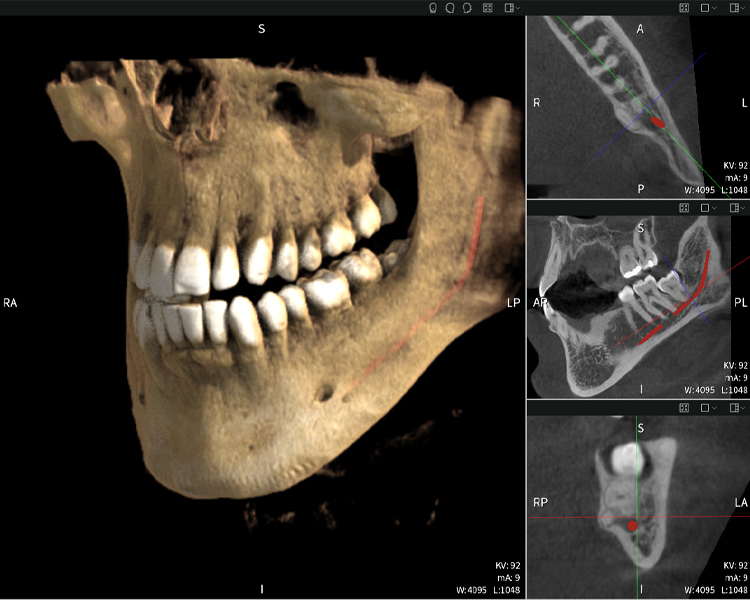

Abbildungen b–d zeigen verschiedene Ansichten einer 3D-Rekonstruktion des Unterkiefers und bieten eine umfassende Übersicht über die Anatomie des Unterkiefers, die Lage der Nerven im Verhältnis zu den Zähnen und ermöglichen die Beurteilung der Zahnsymmetrie und Ausrichtung.